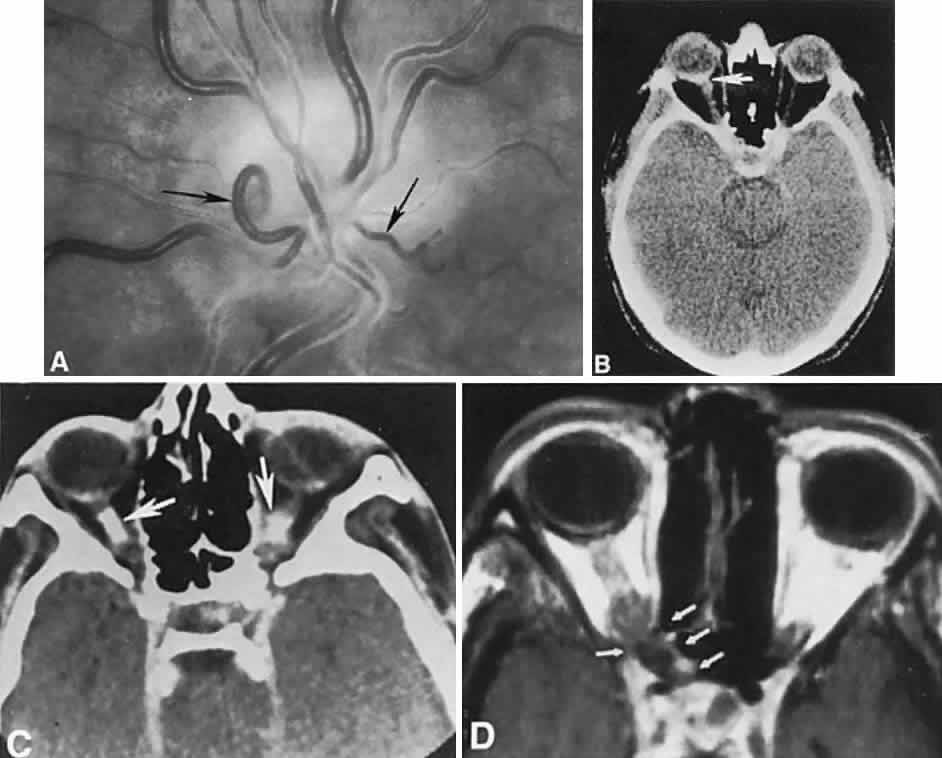

With acute infarction, the retina becomes opaque and takes on a creamy or gray appearance. Atheromatous material in the form of “bright plaques” of cholesterol or other microemboli may be seen, especially lodged at arterial bifurcations (Fig. 5). Segmental arteriolar mural opacification (see Fig. 5D) may follow retinal microembolization by weeks to months, and such sheathing may be as useful as the recognition of the cholesterol embolus itself.43 ERG may show diminished B-wave amplitude, a finding indicating inner retinal ischemia. Weeks following retinal infarction, the optic disc becomes pale, and the arterial tree becomes narrowed in the sector corresponding to the arterial occlusion.

Fig. 5. Retinal microembolic phenomena. A. Bright cholesterol plaque (arrow) impacted at an arterial bifurcation. Thin crystal does not obstruct flow. B. Cholesterol crystals in disc vessels (arrows). Often, the plaque appears larger than the vessel diameter. C. Infarcted opaque retina. The artery contains emboli (? fibrin platelets) that have obstructed flow. D. Reactive opacification of the arterial wall. Fluorescein angiography demonstrated flow through this formerly occluded vessel.

The retinal variety may be admixed in a person who suffers the more conventional attacks of migraine. It is presumed that vasospasm in the retinal circulation determines transient hypoxia, perhaps somewhat similar to the visual cortical event. On rare occasions, the fundus has been examined during typical retinal migraine episodes, and arterial constriction has been described. Wolter and Burchfield106 photographically documented such an episode and demonstrated mild “retinal edema”; vessel narrowing is also evident (Fig. 8). Fortunately, permanent complications of retinal migraine are rare. These may take the form of central retinal artery occlusion or ischemic papillopathy (see Volume 2, Chapter 16); nerve fiber bundle visual field defects may be demonstrated (Fig. 9).

Fig. 8. Retinal migraine. A. During amaurotic episode. Note the dusky appearance of the fundus, increased retinal sheen (possibly edema), and dark narrowed veins (arrows). The disc is also hyperemic. B. Fundus after episode. Compare paired arrows. (Courtesy of Dr. J. Reimer Wolter)